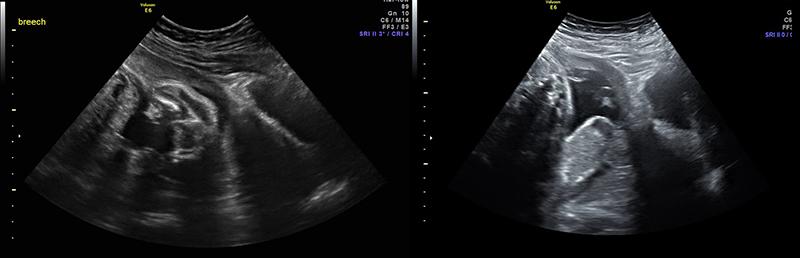

Figure 32A. Two completely separate chorionic and amniotic sacs are visible. Two different eggs were fertilized and the children will be fraternal not identical twins. Note, it can be difficult to distinguish dichorionic diamniotic from other types of twins such as diamniotic monochorionic, especially early in pregnancy.

Figure 32B. Two completely separate chorionic and amniotic sacs are visible. Two different eggs were fertilized and the children will be fraternal not identical twins. Note, it can be difficult to distinguish dichorionic diamniotic from other types of twins such as diamniotic monochorionic, especially early in pregnancy.

Figure 33A. Two separate sacs are visible. In this case dichorionic diamniotic, but could also be monochorionic but not monoamniotic, in which the fetuses would appear to share the same space.

Figure 33B. Two separate sacs are visible. In this case dichorionic diamniotic, but could also be monochorionic but not monoamniotic, in which the fetuses would appear to share the same space.